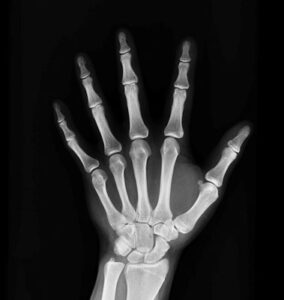

Рентген кисти руки: снимки

Рентген руки — это метод исследования костных структур на предмет переломов, трещин, остеопороза и других патологий. Рентгенологическое обследование — это современная и безопасная медицинская процедура. В 90% случаев это позволяет достоверно установить патологию костей и начать лечение на ранней стадии. Принцип действия аппарата Чтобы сделать рентгеновский снимок руки, необходимо использовать специальный аппарат — рентгеновский аппарат. …